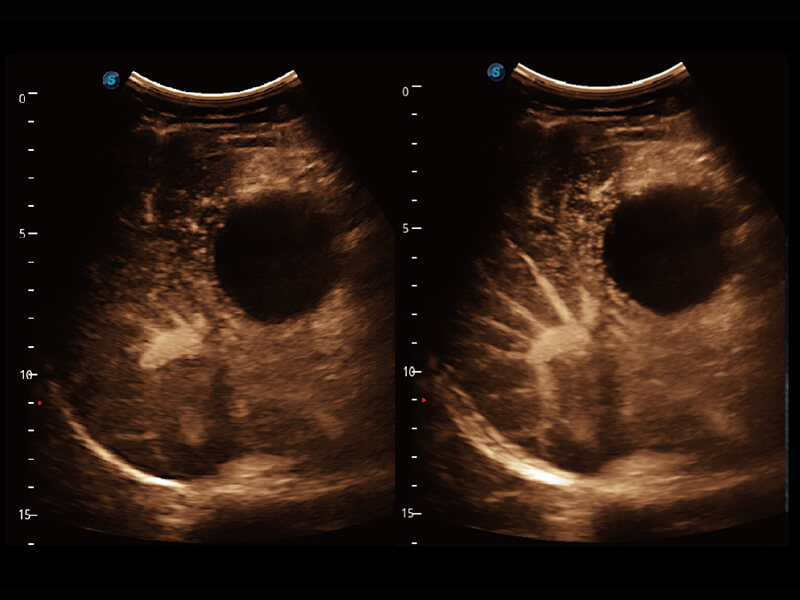

高分辨率容积成像 栩栩如生

超宽频带技术,为容积成像带来优质的二维图像基础,为您呈现丰富的结构细节,栩栩如生地展示宝宝的宫内形态以及各种组织的立体结构。